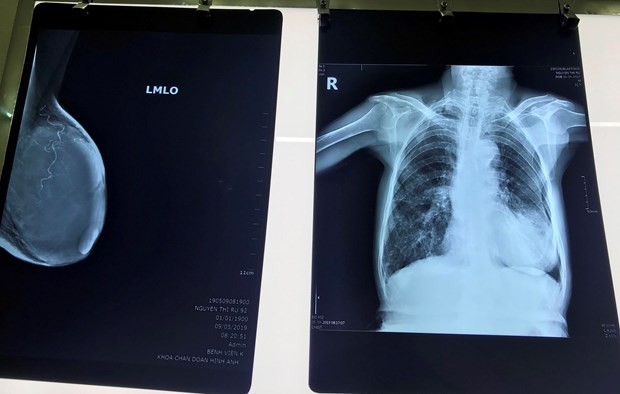

Phim chụp khối u của bệnh nhân. (Ảnh: PV/Vietnam+)

Sau khi các bác sỹ thăm khám, chụp chiếu, kết quả cho thấy khối u kích thước 10x6cm chiếm toàn bộ vú trái bệnh nhân, được chẩn đoán ung thư vú giai đoạn tiến triển.

Sau 2 giờ, kíp phẫu thuật đã thực hiện cắt toàn bộ tuyến vú, loại bỏ tổn thương kích thước 10x6cm cho cụ R.